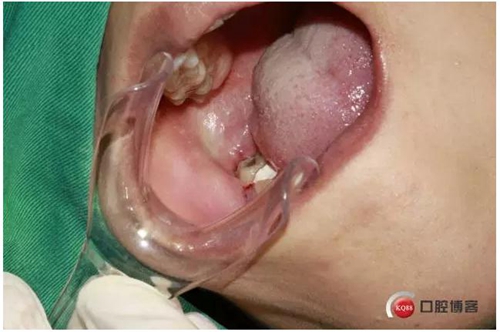

4%鹽酸阿替卡因腎上腺素局部麻醉,

1500633014_991977.jpg

口內(nèi)照片,48遠(yuǎn)中三分之一覆蓋部分牙齦。